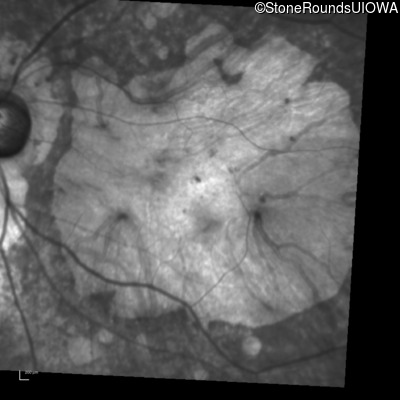

Blue Autofluorescence - Right - Unable to Quantify

Exemplar

Blue Autofluorescence - Left - Unable to Quantify